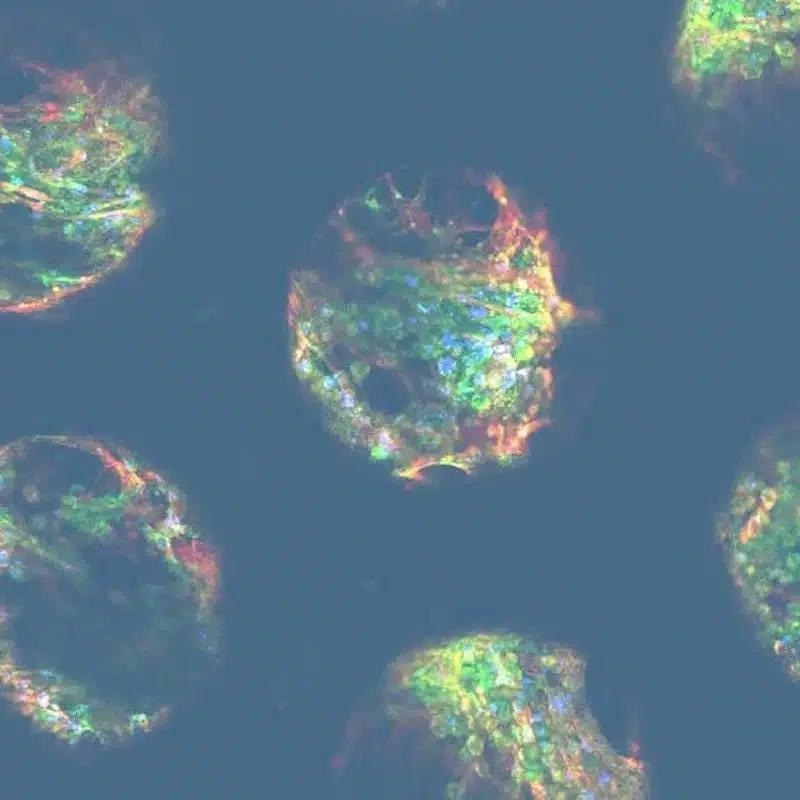

Image Credit: CN-Bio